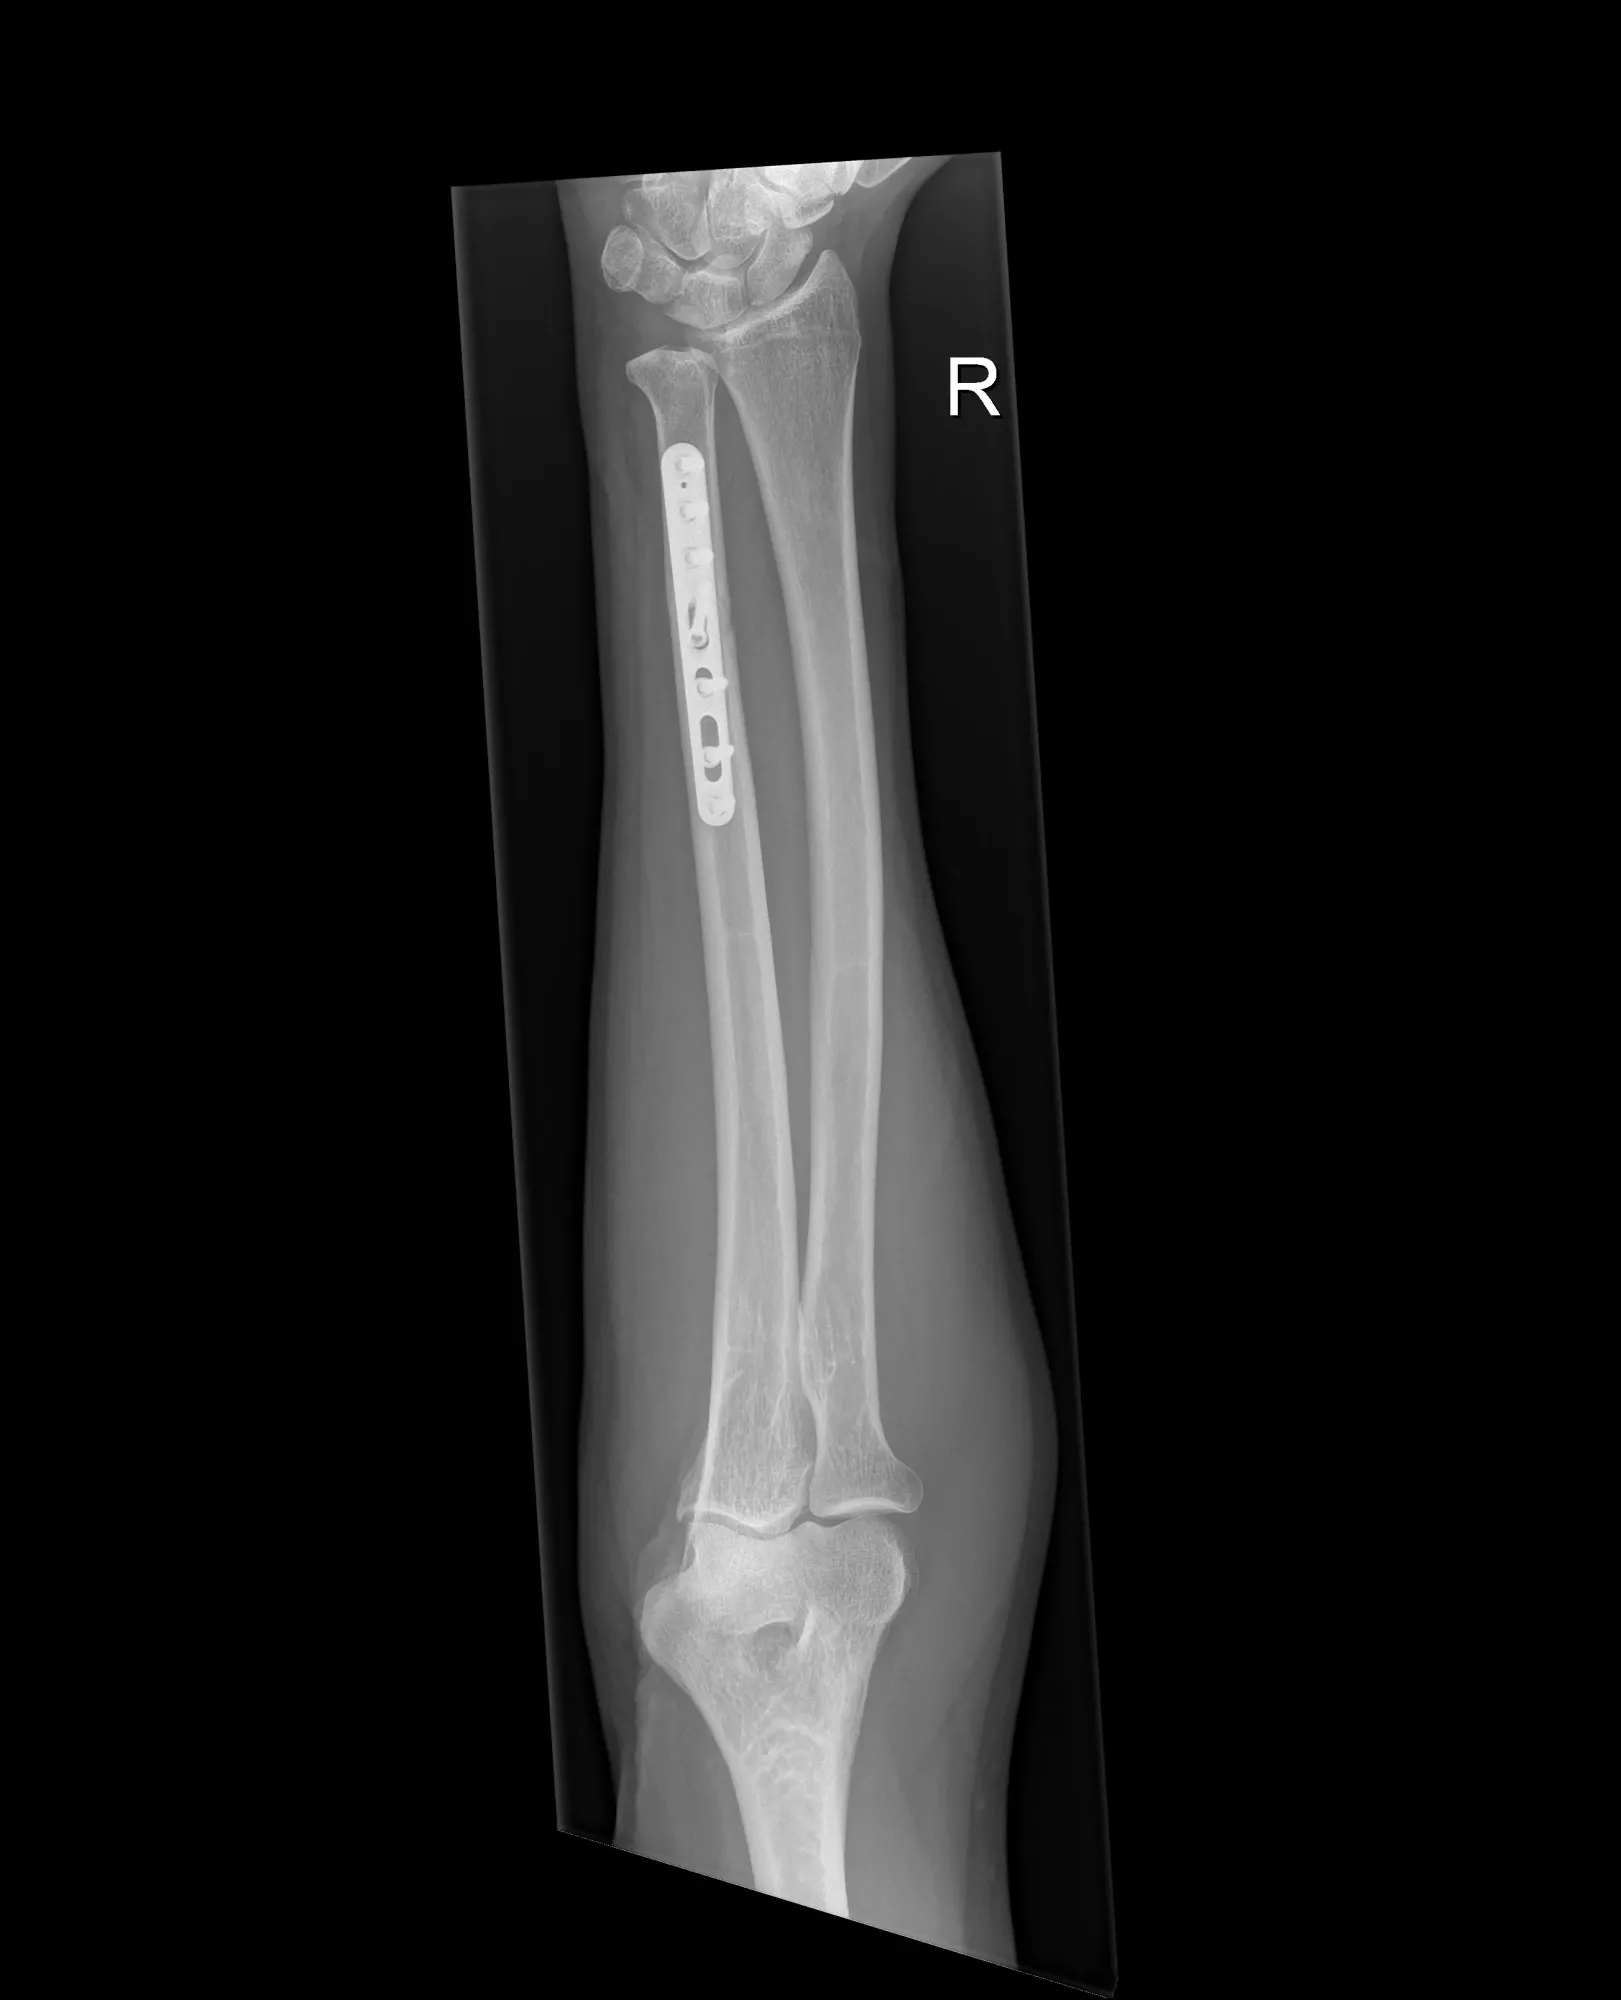

- Verkorting van de ulna

- De ellepijp wordt doorgezaagd, verkort en opnieuw vastgezet met een plaat en schroeven

- Bij kleine correcties kan de verkorting gebeuren via een polsartroscopie (kijkoperatie van de pols)

- In dagziekenhuis, meestal onder plexusverdoving

Nabehandeling

- Gips of brace gedurende 2–6 weken

- Pas belasten wanneer het bot genezen is: → vroegst na 6 weken, soms pas na enkele maanden

- Mogelijke complicatie: non-union (bot groeit niet vast)

- De plaat wordt soms later verwijderd als ze hinder geeft